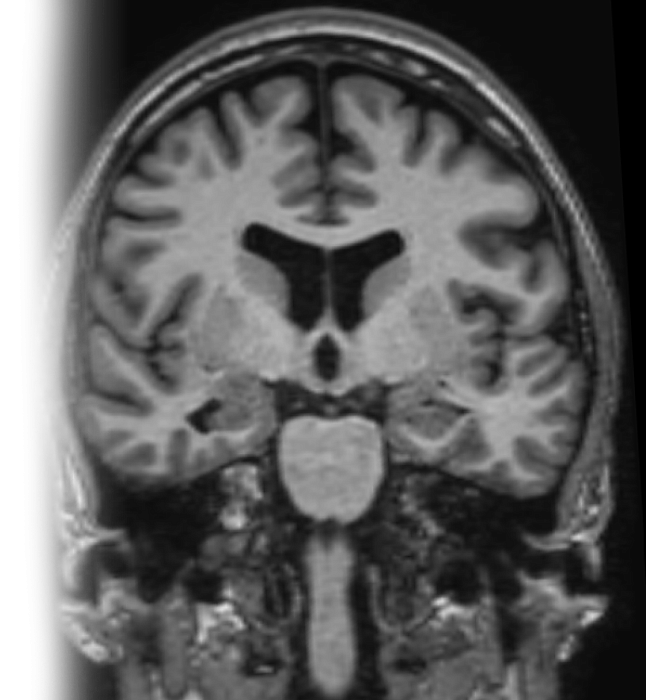

МРТ гиппокампов

Магнитно-резонансная томография гиппокампов – важный метод исследования, который позволяет оценить состояние гиппокампов.